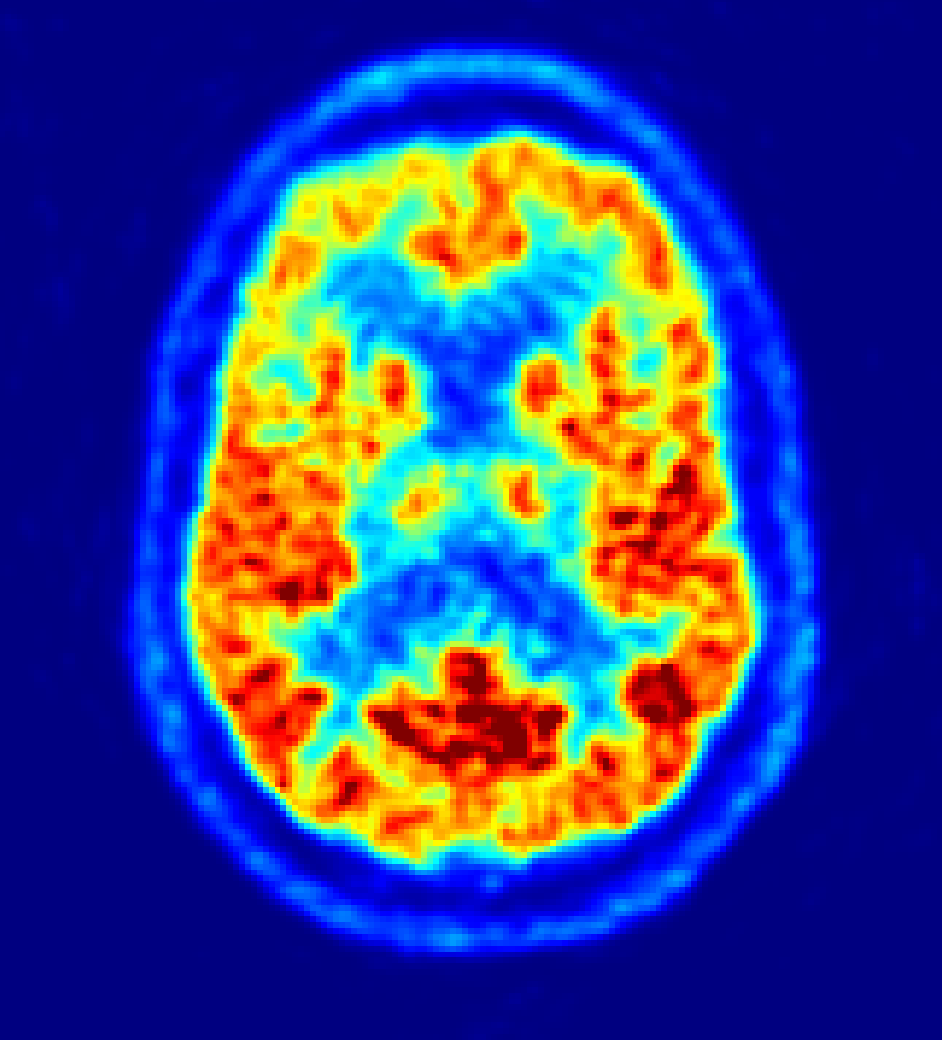

Some steps from visual to numerical assessment:

2. SUVr

| VOI | SUVr |

|---|---|

| Frontal L | 0.88 |

| Frontal R | 1.08 |

| Occipital L | 2.16 |

| Occipital R | 2.04 |

| WM | 0.71 |

| Cerebellum GM | 1.0 (ref.) |

3. Percentile or z-score of SUVr w/ respect to normal population

| VOI | z-score |

| Frontal L | -3.01 |

| Frontal R | -1.45 |

| Occipital L | 0.43 |

| Occipital R | 0.23 |

| WM | 1.12 |

| Cerebellum GM | --- (ref.) |